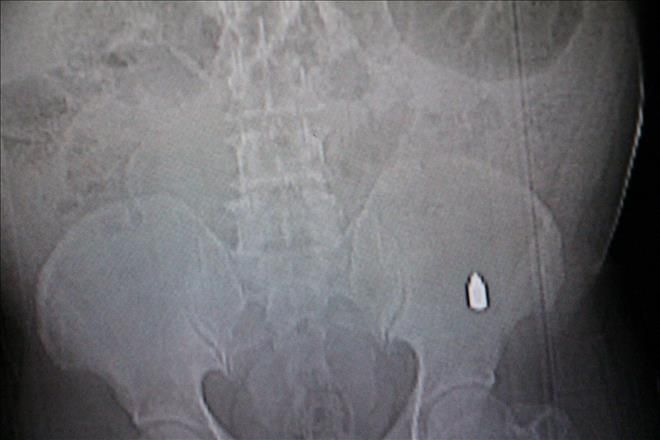

Nusaybin Kışla Mahallesi cumhuriyet ilköğretim okulu mevkide ki boş arsa yanında yürüyen Mehmet Salih Sarohan(51).´´in tespihi yere düşünce eğilip aldığı sırada nerden geldiği belirlenmeyen tabanca kurşunu beline saplandı. Sarohan, çocuklar belki taş atı diye ondan belim acıyor, tahmininde bulundu. Hemen olay yerinde yakınlarına anlatı. Yakınları da Sarohan´ın beline baktı ki bir yara izidir. Yaralı Sarohan yakınları tarafından Nusaybin devlet hastanesi acil servisine kaldırıldı. Burada tedavi altına alındı. Sarohan´ın Rongen filmi çekilince belinde tabanca kurşunu gibi bir cisim belirlendi. Cisim Sarohan´ın belindeki et içine saplanmış gibi gözüktüğü öğrenildi. Sarohan hastaneye yatırılarak kontrol altına alındı. Olayla ilgili polis ekipleri soruşturma başlattı.-Haber-Ahmet Akkuş